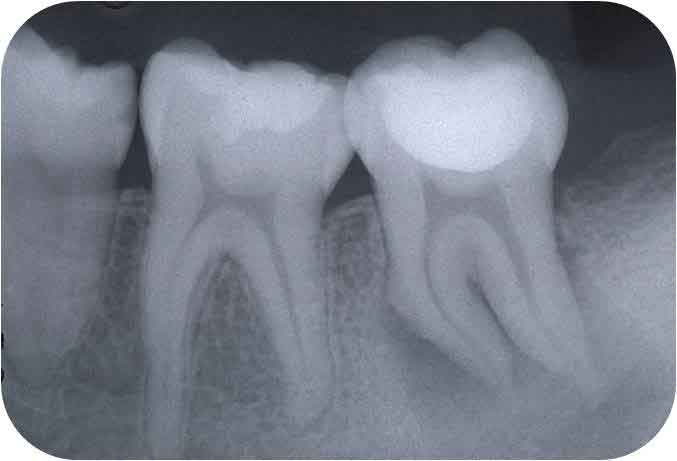

これが、根管が大きく(若年者であることが多い)、それも弯曲しているとなると、話がかわります。

根管が大きい=象牙質が薄い

という条件で、必要十分な拡大・形成を行い、歯根破折を起こさないようにできるだけ長く延命させていくということは、ストレートな根管であれば、慎重にファイルサイズを上げていくことで達成は可能だと思います。

一方、「ファイルサイズを上げる」 ということは 「ファイルのしなりがなくなる」 ということを意味するため、弯曲根管においては、通常の方法で治療を進めて行くに伴って、その弯曲部を無意識に、不用意につぶしていくことになります。

この結果、歯の脆弱化が進み、さらに抗原性の物質を取り残す可能性がある。

そこそこ細くて弯曲している根管より遙かに難しいのが、写真のような「太くて弯曲している根管」なのです。